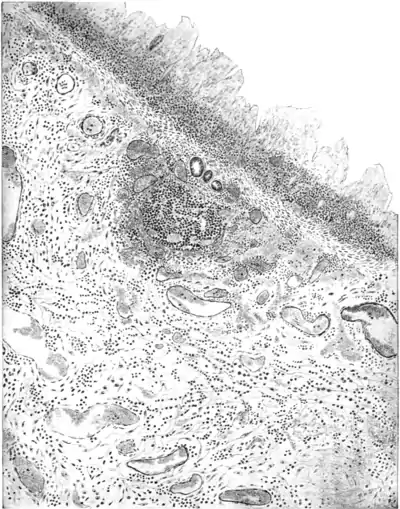

Microscopical section of the large intestine in bacillary dysentery, showing necrosis of the mucosa, cellular infiltration and hæmorrhages into the submucosa. (After Bahr.)

Plate VIII.